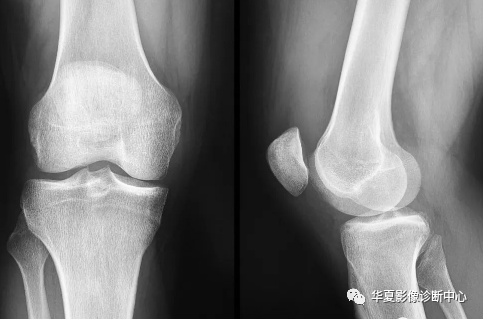

An tear on this knee radiograph with (almost) 100% confidence – can you see why?

(几乎)100% 的信心诊断膝关节 X 线片上有ACL撕裂 – 你知道为什么吗?

股骨外侧髁“深沟”征(Lateral femoral “notch” sign)

前十字韧带撕裂:

前十字韧带起于股骨外髁内侧面后部,向前内下方走行,止于胫骨髁间粗隆前方及外侧半月板前角。其正常时维特膝关节前后方稳定,参于限制膝关节过伸,协调关节旋转活动,限制内外翻活动。由于膝关节过伸或外展,过度展曲、内收、旋转均可引起损伤撕裂。